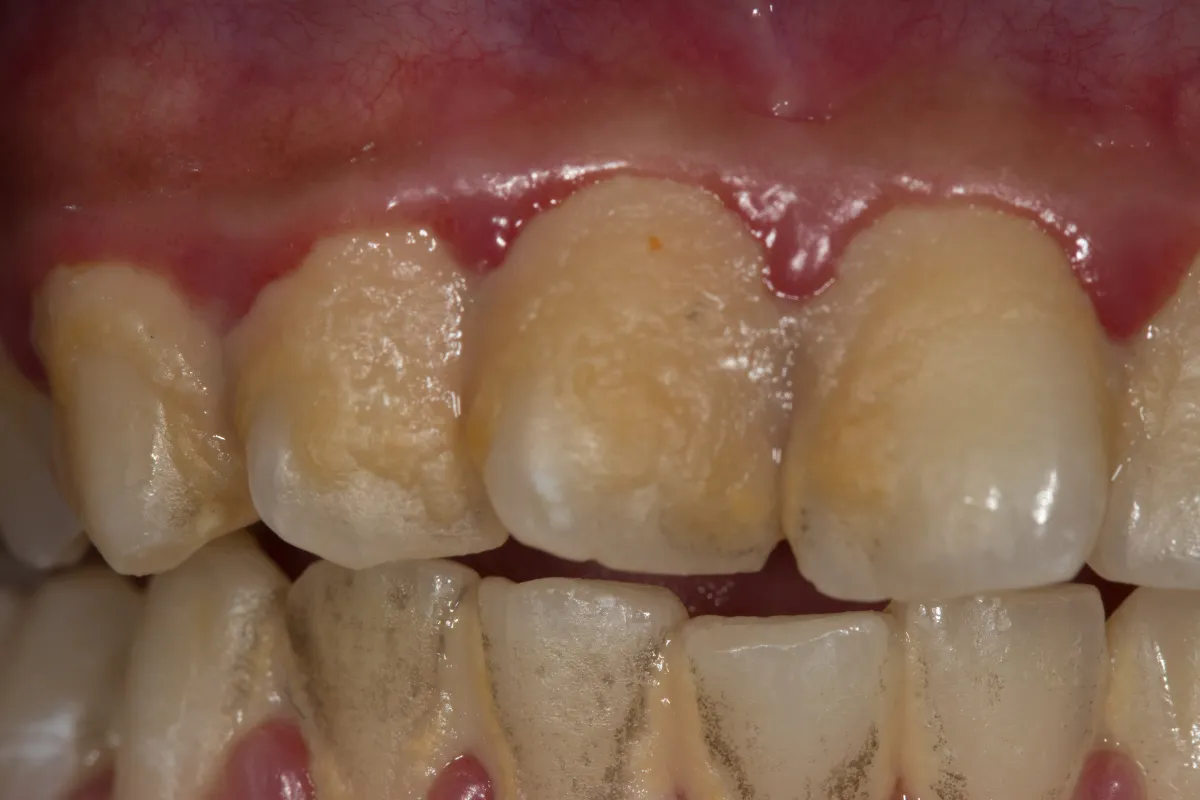

Kiedy brązowa plamka to coś więcej niż osad? Jak odróżnić przebarwienie od próchnicy

Bardzo często pacjenci martwią się, że brązowa plamka na zębie to już próchnica. To słuszna obawa! Kluczowe jest rozróżnienie tych dwóch problemów. Brązowy osad to jedynie przebarwienie powierzchniowe, które osadza się na szkliwie i nie niszczy jego struktury. Próchnica natomiast to choroba bakteryjna, która prowadzi do demineralizacji i stopniowego niszczenia tkanki zęba, tworząc ubytek. Początkowa próchnica może wyglądać jak biała, matowa plamka, która z czasem ciemnieje. Jeśli masz wątpliwości, zawsze konieczna jest konsultacja ze stomatologiem. Tylko profesjonalista jest w stanie prawidłowo zdiagnozować problem i podjąć odpowiednie leczenie.